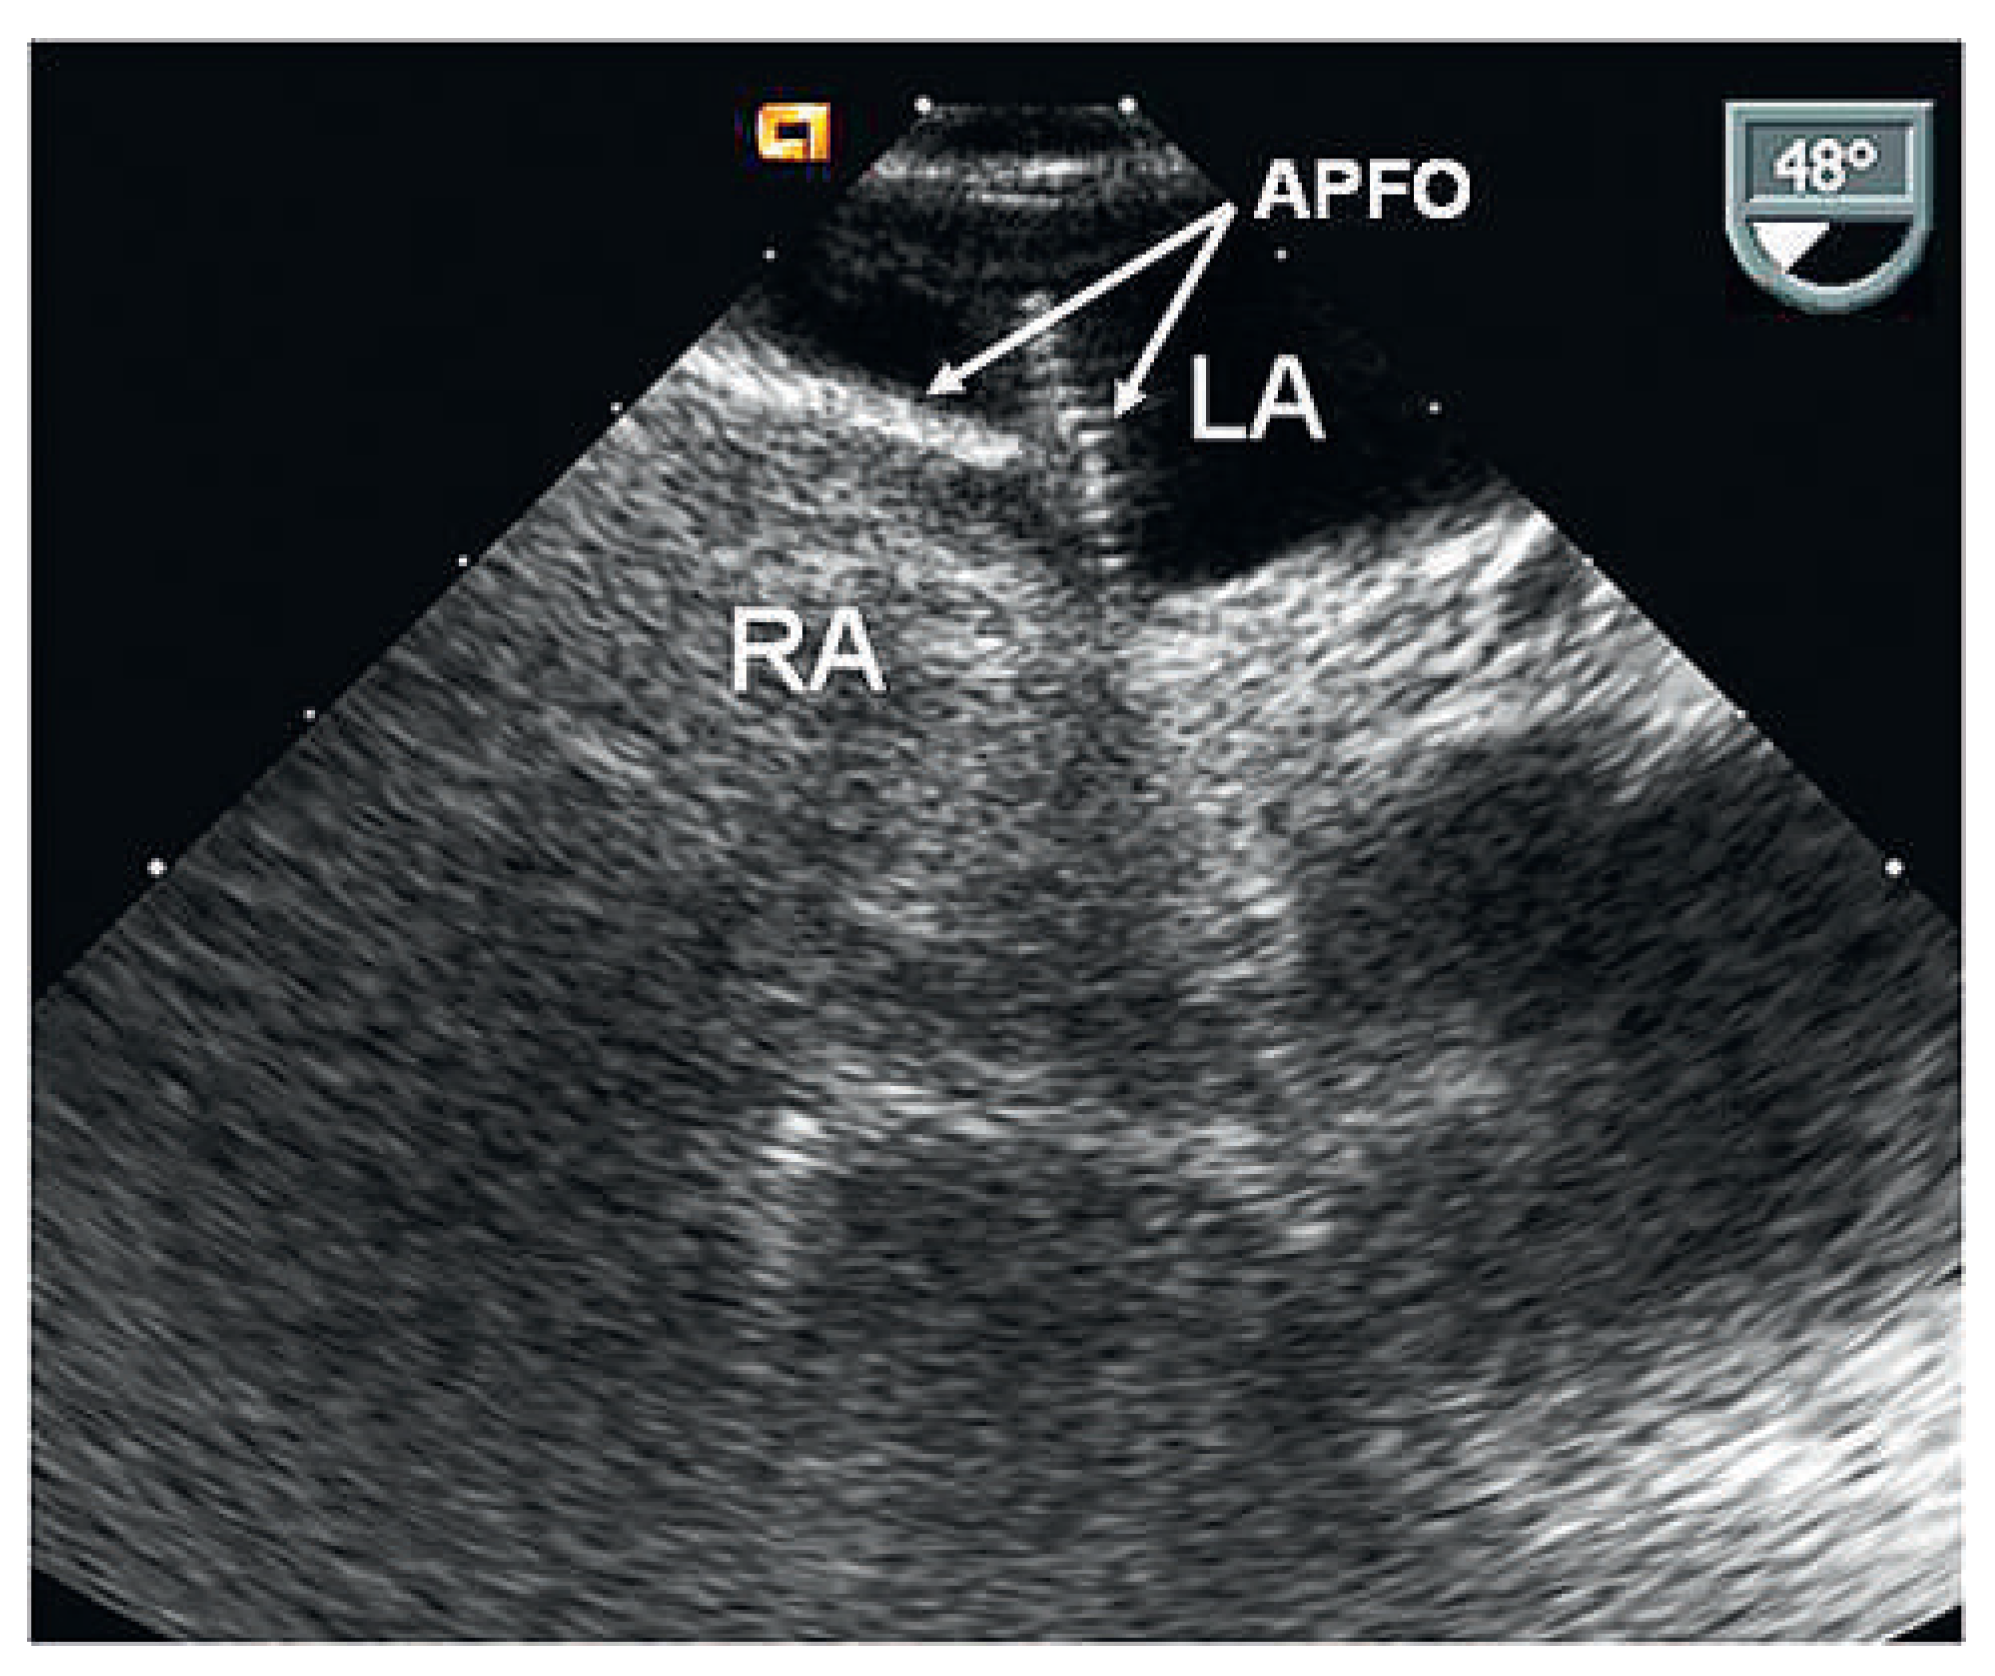

Figure 2. Contrast TEE 6 months after implantation with residual shunt grade III. APFO = 30-mm Amplatzer PFO Occluder; LA = left atrium; RA = right atrium.

Six months later, follow-up contrast TOE documented a residual shunt grade III (Figure 2). Using the same technique, a second 25-mm APFO was implanted (Figure 3). Contrast TTE performed the next day did not detect any residual shunt. Clopidogrel 75 mg was again prescribed for 1 month and acetylsalicylic acid 100 mg for 5 months.